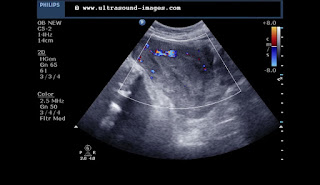

Colour Doppler ultrasound shows mild vascularity around the left adnexal region- nothing significant there: